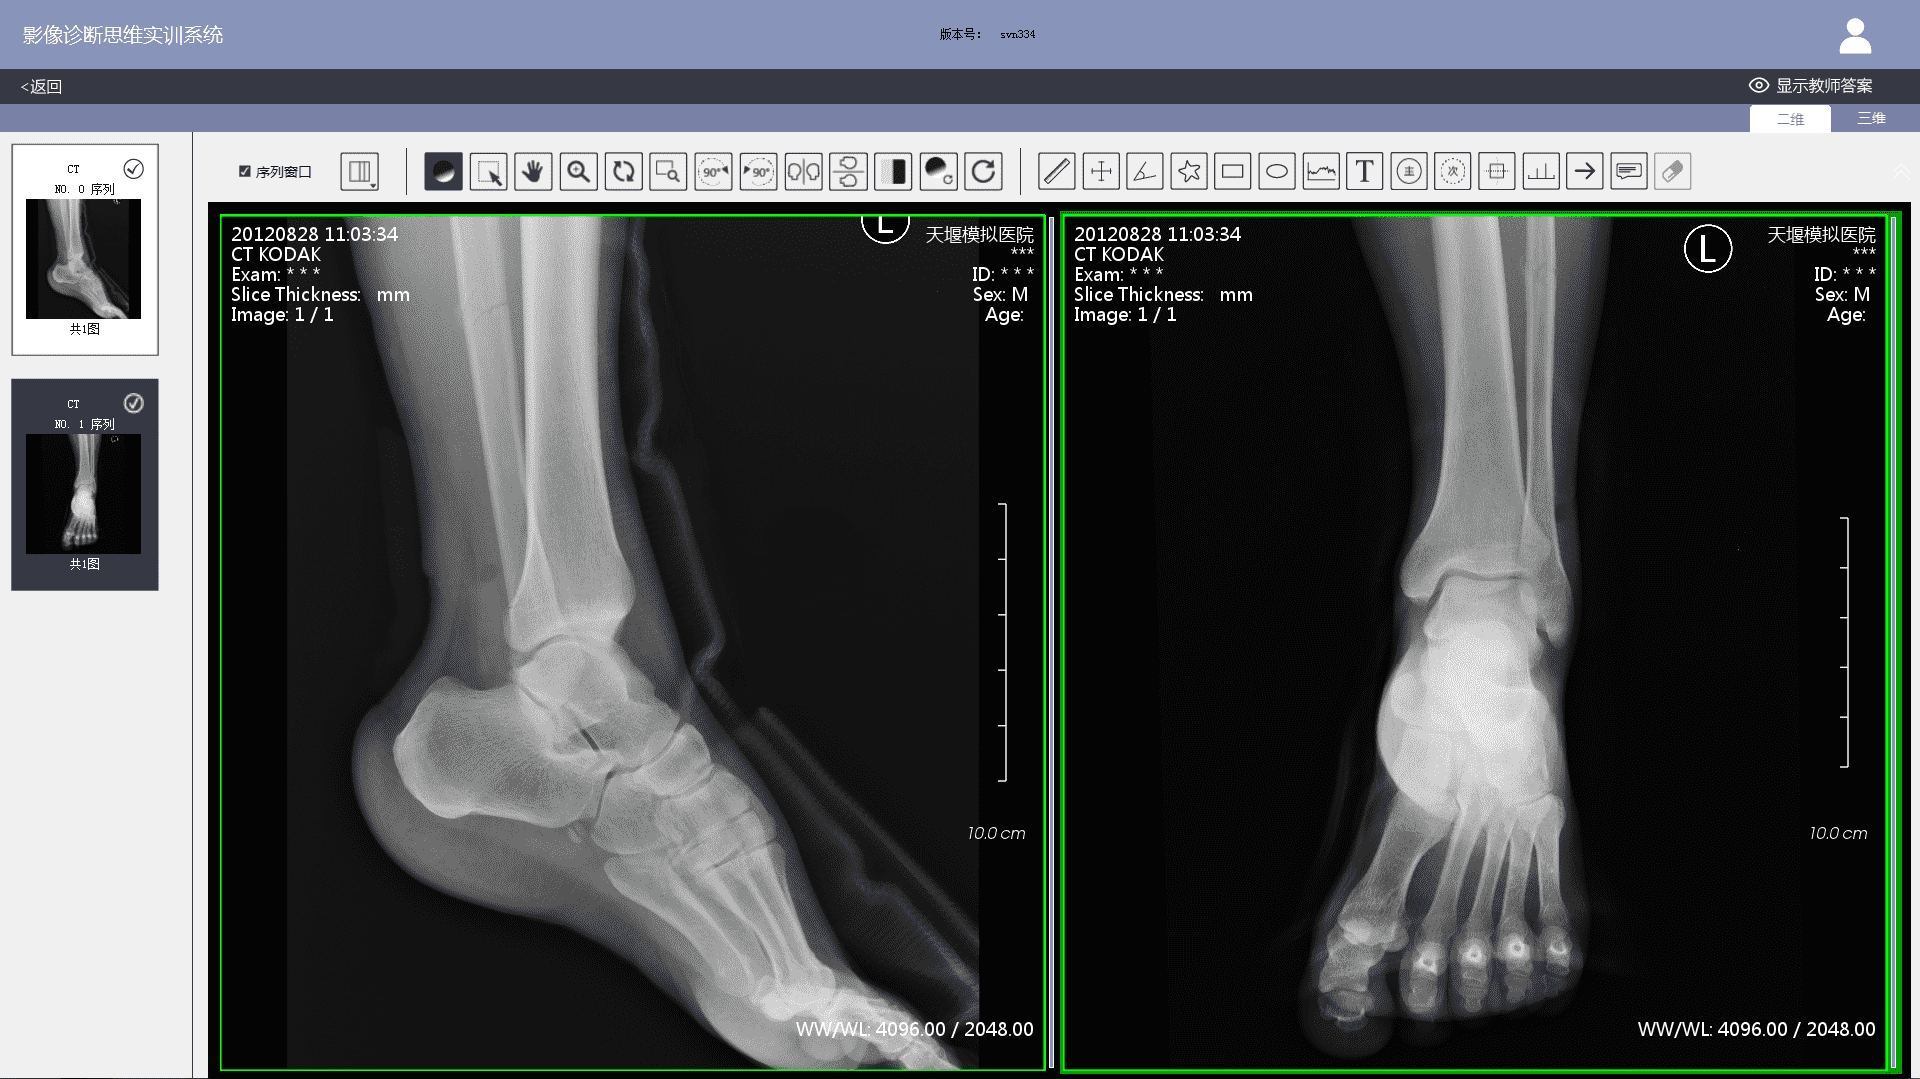

3)  Imaging workstation: The system comes with an imaging workstation and all cases can be loaded with DICOM files. Teachers can post-progress them according to actual teaching needs. The post-processing function meets the basic requirements of a common clinical imaging workstation, including: 1) layout. Users can choose 1X1, 1X2, 2X1, 2X2, 2X3, 3X3, etc.; 2) Window width and level adjustments; 3) Zoom in and out; 4) Zoom in on the area of interest; 5) Left turn 90 degrees; 6) Right turn 90 degrees; 7) Left and right mirror flip; 8) Up and down mirror flip; 9) Negative film; 10) Distance measurement; 11) Two-way ruler; 12) Angle measurement; 13) Polygon measurement; 14) Adding notes & comments; 15) Labeling major signs; 16) Labeling secondary signs, etc.

3)  When viewing case images, students can post-process DICOM files on the imaging workstation to observe positive and negative imaging signs in greater detail. After finishing a case exercise, student's test results, the correct diagnosis report and the comparison of the thinking processes will show. Students can also participate in image thinking case assessment set up by teachers.